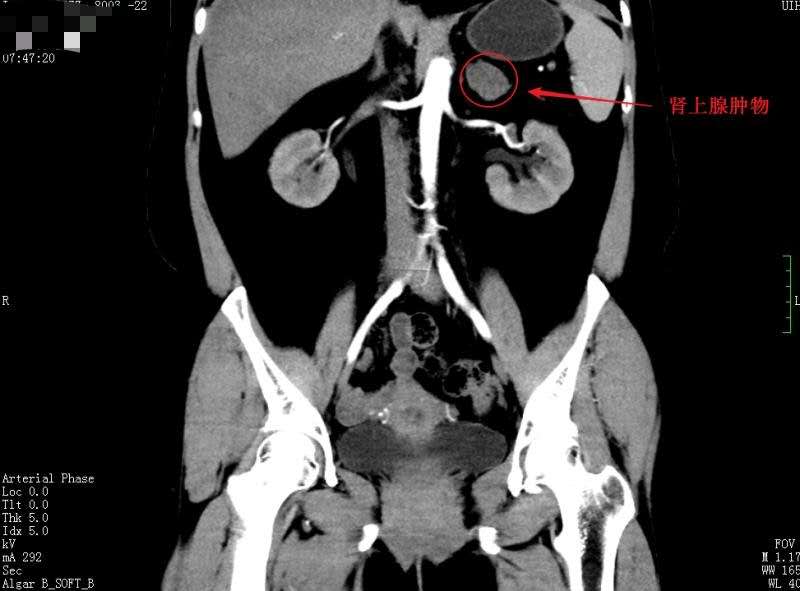

泌尿四科,通过详细检查后发现,刘女士的肾上腺上有个“鹌鹑蛋”大小的肿瘤,这个肿瘤分泌了大量的激素,引起身体代谢紊乱,这才导致了刘女士“满月脸”肥胖、高血压等症状。

经过精心术前准备,泌尿四科杨科主任为首的团队成功为刘女士在腹腔镜下实施了左侧肾上腺肿物切除术,目前刘女士的血压由入院时的220/130mmHg降至130/90mmHg左右,趋于正常,头晕、心慌症状也明显改善,激素替代疗法正在循序递减。